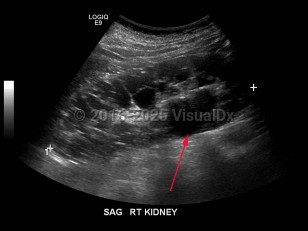

Polycystic kidney disease

Polycystic kidney disease (PKD) is an autosomal dominant (or, less often, autosomal recessive) disorder characterized by numerous cysts in the kidneys, which may lead to end-stage renal failure. The autosomal dominant trait is associated with mutations in either PKD1 (which encodes polycystin-1) or PKD2 (which encodes polycystin-2). A minority of patients with PKD have a defect unrelated to PKD1 or PKD2. PKD1 mutations are more common and correlate with an earlier age of disease onset as well as more rapid decline in renal function.